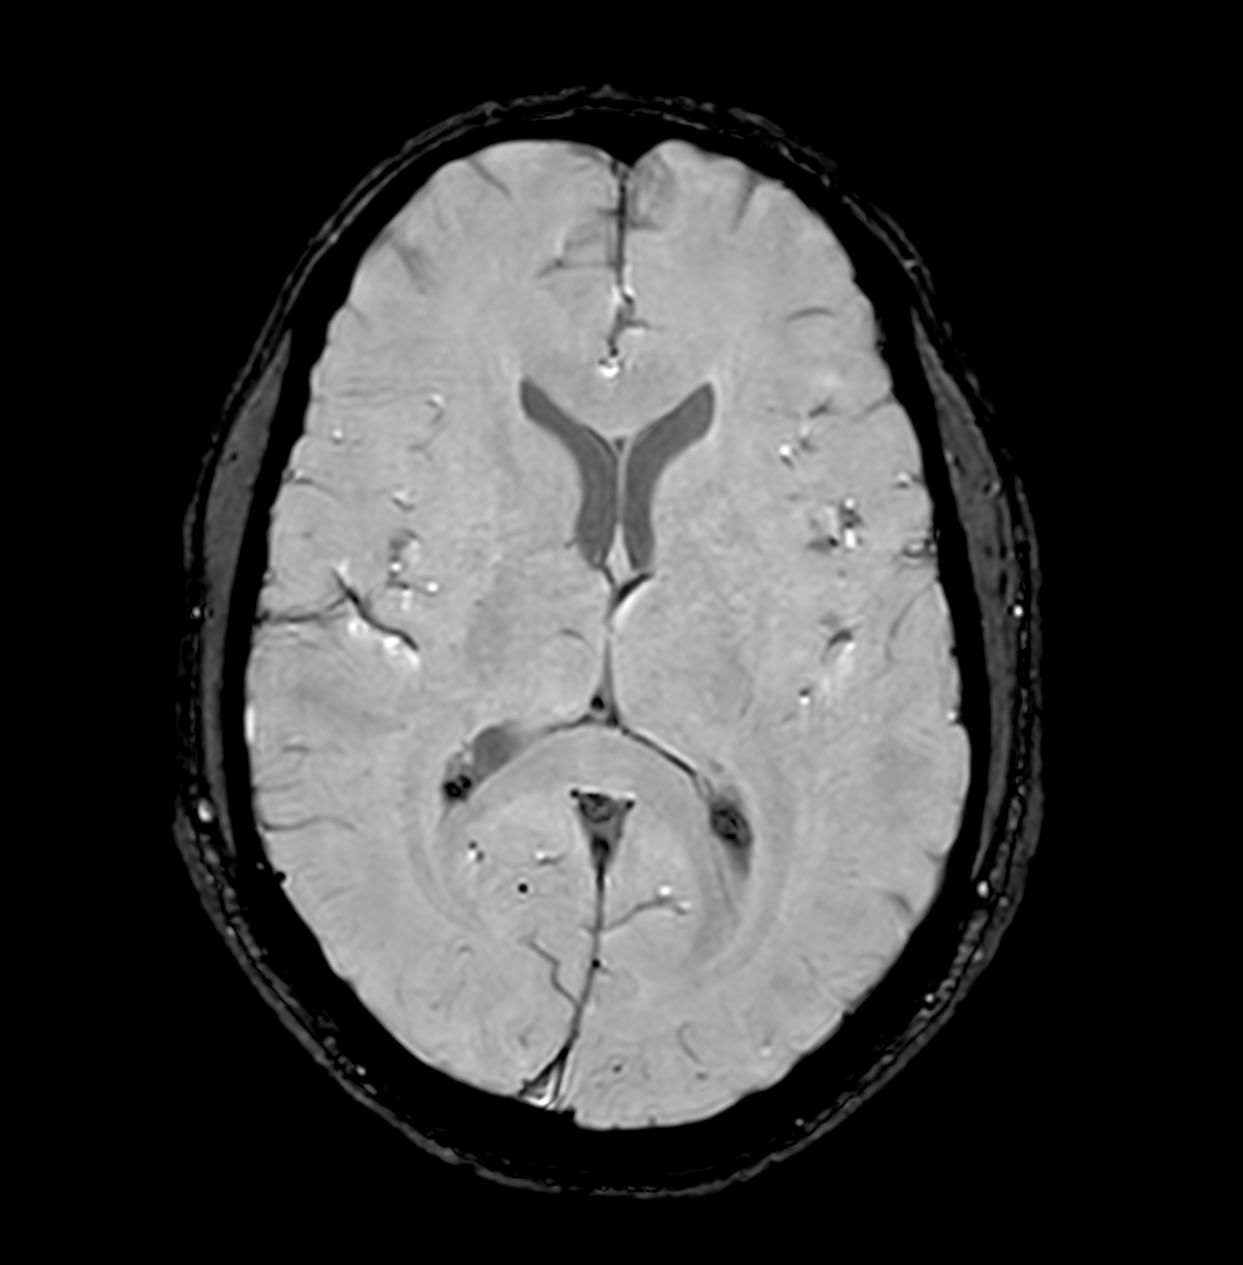

Alzheimer’s Disease Anti-Amyloid Immunotherapies (ARIA) 1.5T

Amyloid clearing medication, such as Aduhelm (Aducanumab) and Leqembi (Lecanemab) have been cleared by the FDA in 2022/2023, to slow down cognitive decline in early-stage Alzheimer’s disease. ASNR-recommendations for AD therapeutic imaging were published in 2022 for eligibility assessment as well as for monitoring for amyloid-related imaging abnormalities. This ExamCard includes ASNR-recommended consensus protocols for imaging of Alzheimer’s Disease Anti-Amyloid Immunotherapies (ARIA). (Cogswell et al., AJNR 2022,43(9)E19-E35;DOI: https://doi.org/10.3174/ajnr.A7586))